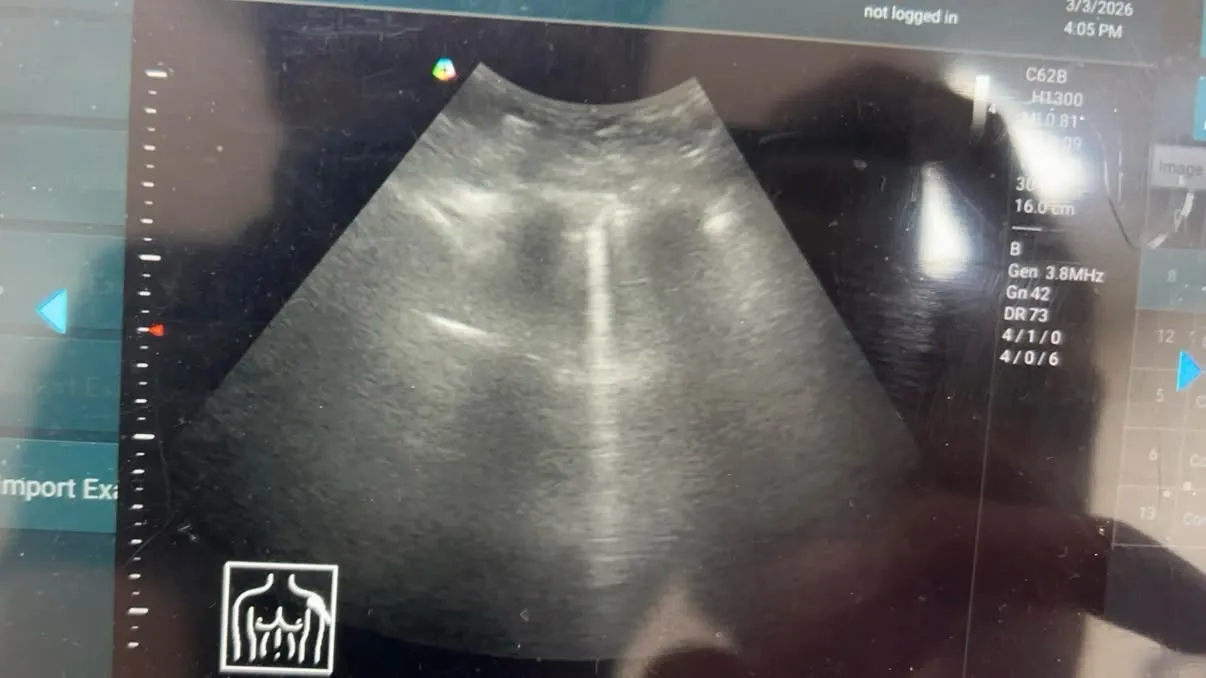

還好診所當初有設置超音波,立馬請病患躺下,心臟沒問題,不過發現左側有B line和些許shred sign(疑似肺炎),基於她是洗腎病患,屬於高風險,於是立刻安排轉到急診去做進一步治療。

基層診所如果有配置超音波真的是一大助力,超音波是新時代的「視」診器,尤其對於判斷肺部、心臟、腎臟和腹部急症,可以快速且非侵入性,可以及早發現問題所在,減少病患在家裡惡化才被發現的機率。